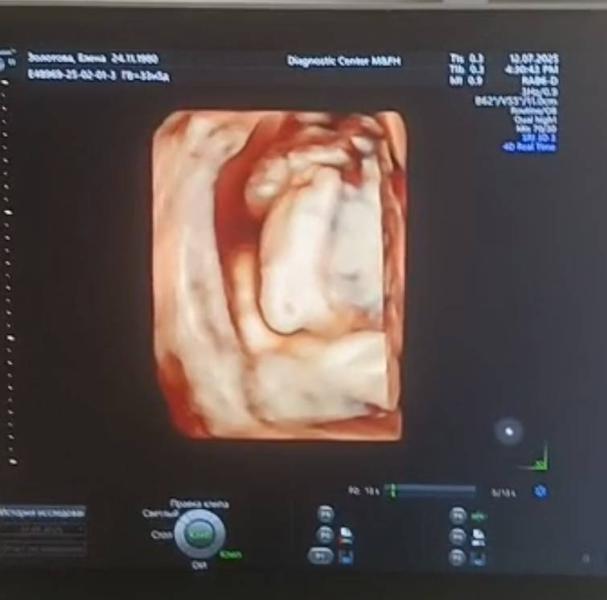

P. S.: на последнем скрининге наша деловая булочка показала свои пяточки во всей красе, и как истинная дочь своего отца, сложила их одну на другую, умилив нас еще более)))